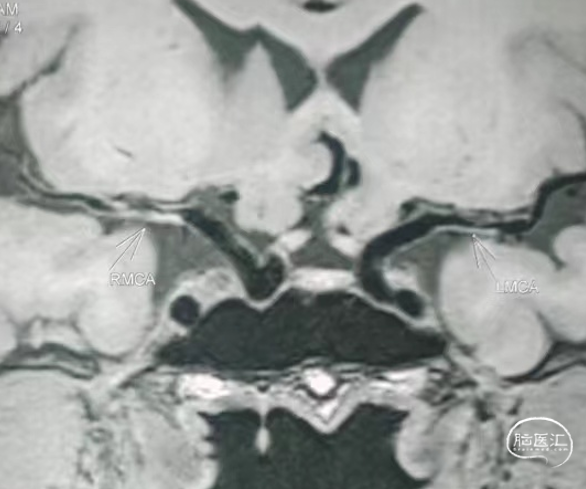

➢术前HRMRI

高分辨核磁提示:双侧大脑中动脉M1段均伴有斑块增生强化,管腔狭窄。